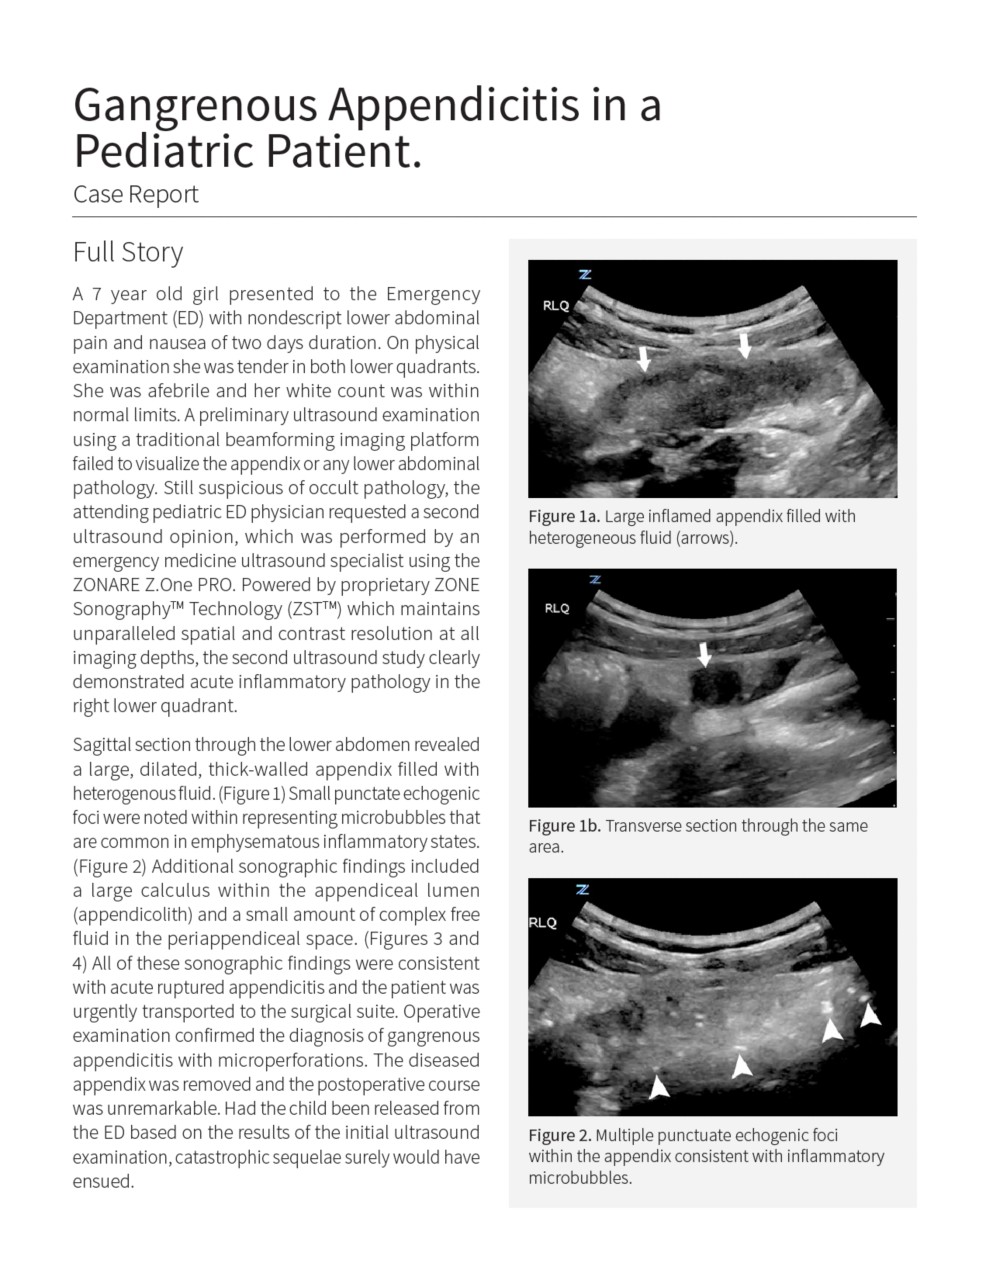

Pediatric Gangrenous Appendicitis